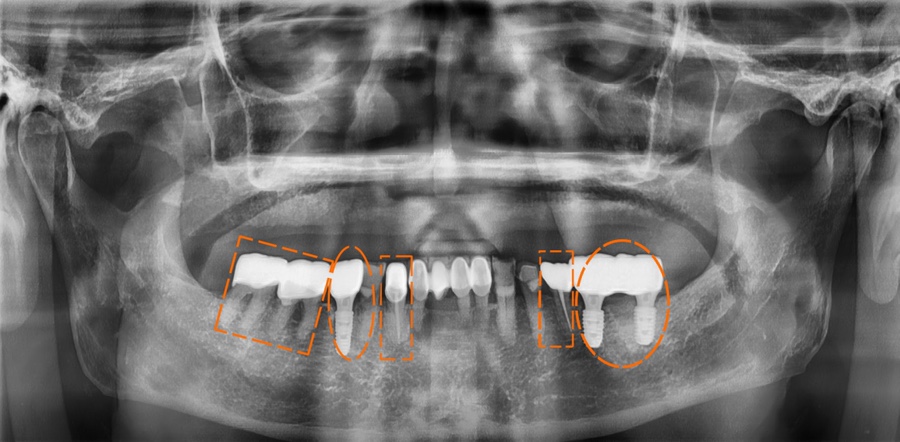

치료 전,후 사진 / 2024. 12. 18~2025.06.19

복합 치료에서 가장 중요한 포인트

복합적인 치과 치료에서는 단순히 개별 치료를 잘하는 것보다 전체적인 균형을 고려하는 것이 중요합니다.

한 부위만 치료한다고 해서 문제가 해결되는 것이 아니라, 전체 치아의 기능과 교합이 함께 맞아야 장기적으로 안정적인 결과를 얻을 수 있기 때문입니다.

또한 치료 시기를 놓치지 않는 것도 중요합니다. 초기에는 간단한 치료로 해결할 수 있었던 문제가 방치될 경우, 신경치료나 임플란트까지 이어질 수 있기 때문에 조기 진단과 치료가 필요합니다.

결국 치과 치료는 단편적인 접근이 아닌, 전체적인 구강 상태를 고려한 계획적인 치료가 핵심이라고 할 수 있습니다.

복합적인 치과 치료가 필요하다고 해서 무조건 복잡하고 오래 걸리는 건 아닙니다. 정확한 진단과 계획적인 접근으로, 치료 기간과 비용을 효율적으로 조절할 수 있습니다.

*치료 기간 : 2024. 12. 18~2025.06.19